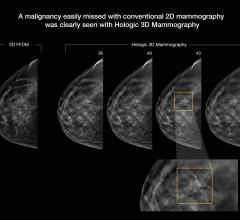

Just a few short years ago, the only options for breast imaging were 2-D mammography, but thanks to rapidly advancing ...